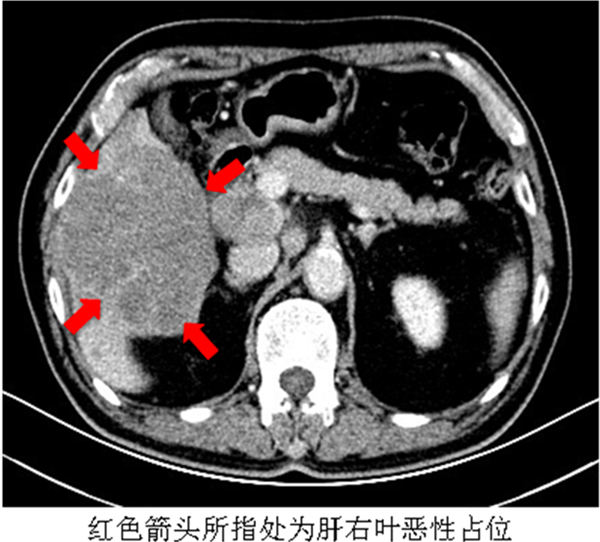

今年2月,66岁的刘先生因乏力、肝区不适就诊于北京燕化医院消化科。门诊完善腹部彩超提示肝脏弥漫性损害,腹膜后多发肿大淋巴结。患者既往乙肝病史20余年,未定期复查。门诊医生判断患者可能存在肝脏恶性肿瘤,于是将刘先生收入院系统诊治。入院后完善肿瘤标志物,发现肝癌标志物甲胎蛋白明显升高。腹盆腔增强CT提示肝右叶下段恶性占位,大小约100×85mm,并肝门及腹膜后淋巴结转移。患者原发性肝癌诊断明确,随后相继行2次肝动脉化疗栓塞术,目前生活质量明显下降且生存期有限。

3. 肝脏CT检查

肝癌诊断和鉴别诊断最重要的影像检查方法。用来观察肝癌形态及血供状况、肝癌的检出、定性、分期以及肝癌治疗后复查。腹部平扫价值有限,可用来观察脂肪变、出血和碘油栓塞后沉积情况。增强扫描有诊断价值。